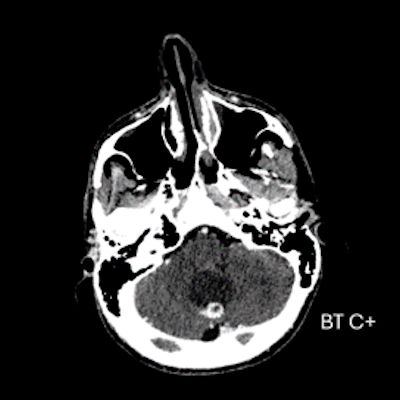

- A) Beyin BT incelemede; posterior fossada hipodens, düzgün sınırlı kistle beraber (oklar), posteriorunda 8 mm boyutunda, iyi sınırlı, kontrastsız BT’de parankim ile izodens, postkontrast görüntülerde yoğun kontrast tutulumu gösteren mural nodül komponenti (oklar) gözlenmektedir.

- BT’de tipik olarak iyi sınırlı, hipodens kistik bir lezyon ve içinde belirgin şekilde kontrastlanan mural nodül izlenir.

- Kontrastlı incelemelerde mural nodül belirgin ve yoğun kontrast tutulumu gösterir. Ancak kist duvarında genellikle kontrastlanma beklenmez.